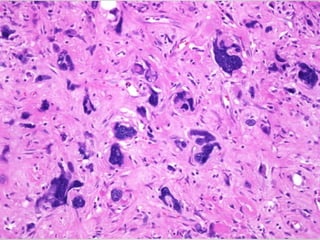

• Pleomorphic liposarcoma

• Sheets of anaplastic cells, bizarre nuclei and variable

amounts of immature adipocytes (lipoblasts).

• #19 Pleomorphic liposarcoma